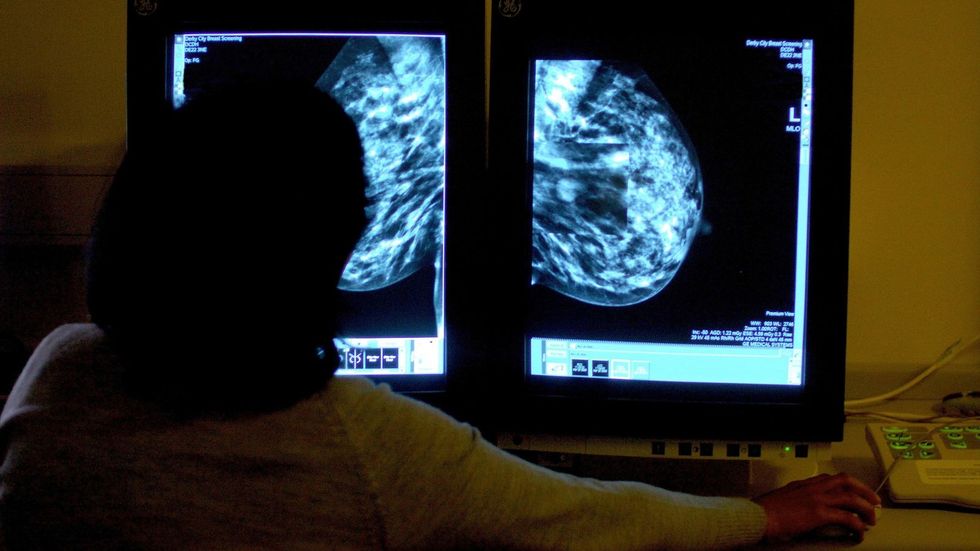

Numri i njerëzve të diagnostikuar me kancer në Mbretërinë e Bashkuar do të rritet me 30 për qind deri në vitin 2040, duke e dërguar numrin e rasteve të reja çdo vit në më shumë se gjysmë milioni.

Nëse tendencat aktuale vazhdojnë, rastet e kancerit do të rriten nga 384 mijë në vit deri në 506 mijë në vitin 2040, sipas analizës së Cancer Research UK.